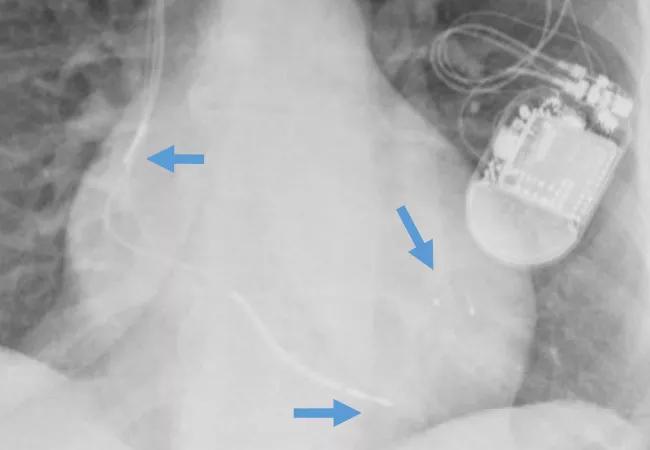

image of a patient with a cardiac resynchronization therapy (CRT) device with arrows pointing to the three leads used in CRT

Image at top shows an implanted CRT device with arrows pointing to the three leads used in cardiac resynchronization therapy.